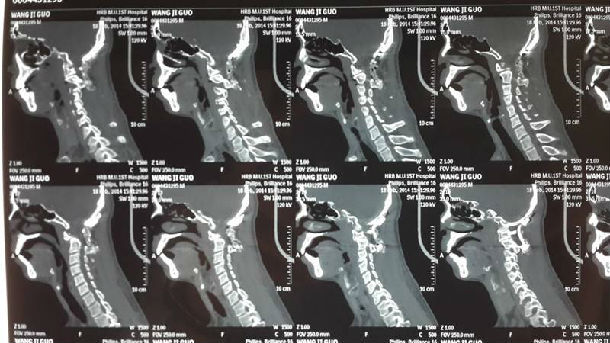

手术前CT显示:寰枢椎脱位

手术后复查CT显示:寰枢椎脱位完全复位,脊髓受压明显改善,枕颈固定位置良好,局部植骨融合。